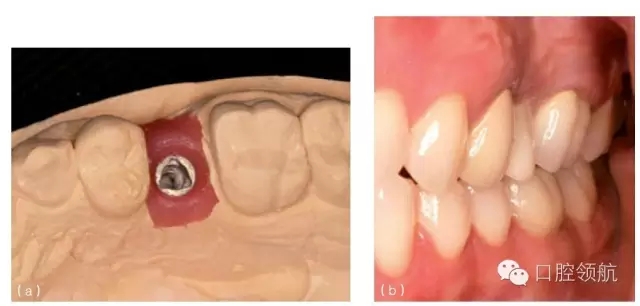

種植體植入時如果太偏舌側(cè),會造成冠修復(fù)時,唇側(cè)頸部凸度異常(圖10.1b,圖10.27),或是冠的瓷層必須蓋過頰側(cè)軟組織以形成理想的頸部外形(圖10.28a~c)。這種覆蓋會使口腔衛(wèi)生的維護更困難,同時也會由于軟組織的根向退縮產(chǎn)生美學(xué)問題。在有的情況下,采用冠覆蓋頰側(cè)軟組織(圖10.29a~c)的設(shè)計也是必需的(類似于某些固定局部義齒的橋體),否則,冠將呈現(xiàn)出明顯的頸部缺損或外形凸度不足的情況(圖10.30a,b和圖31a,b)。

圖10.28 (a)種植體水平印模的模型。注意種植體位于近中稍偏舌側(cè)。(b)為改善頸部外觀,必須采用冠覆蓋頰側(cè)軟組織。(c)全冠要求大量的塑形,并且覆蓋軟組織,以獲得良好的美學(xué)效果。

圖10.29 (a)上頜第一前磨牙種植體位于鄰牙中部近舌側(cè)。(b)冠的牙合面觀,可見牙合面螺絲孔位于冠的舌側(cè)。(c)全冠的唇側(cè)觀,可見大量的烤瓷覆蓋軟組織。